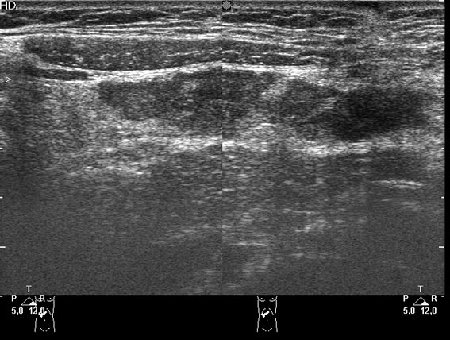

у меня есть в архиве случай, когда мальчику 10 лет назад была выполнена спленэктомия (травма с разрывом, оперировали не у нас, и что там ему делали - непонятно). а я "нашла" селезенку, в типичном месте, S ее составляла 9 см2.

Если в типичном месте и не выполнялась аутотрансплантация, то это может быть гипертрофия т.н. дополнительной селезенки.